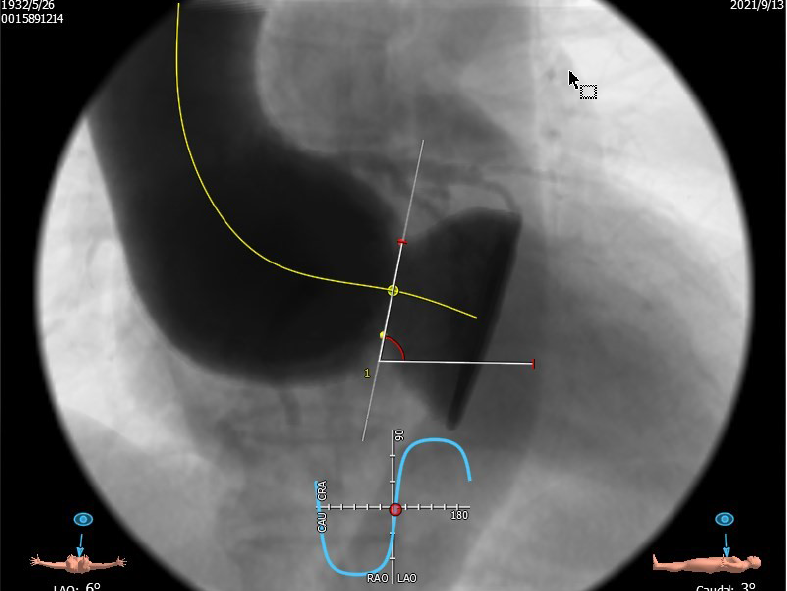

4.患者术中造影角度LAO:5°,CAU:3°。

最佳投照角度:LAO:5°,CAU:3°

主动脉根部角度:80°

升主动脉与主动脉窦部夹角:106°

图3 主动脉瓣大量反流;主动脉瓣环平面几乎与脊柱平行